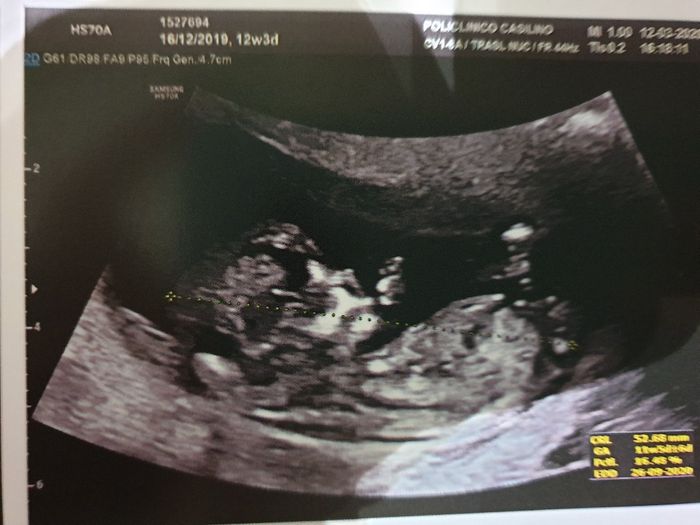

Teoria nub

Da Dadar85 , Il 14 Marzo 2020 alle 09:54

Buona sera,sono alla tredicesima settimana, ho scoperto da pochi giorni la teoria nub, secondo la quale si riuscirebbe a stabilire il sesso del nascituro. Chi di voi ha...